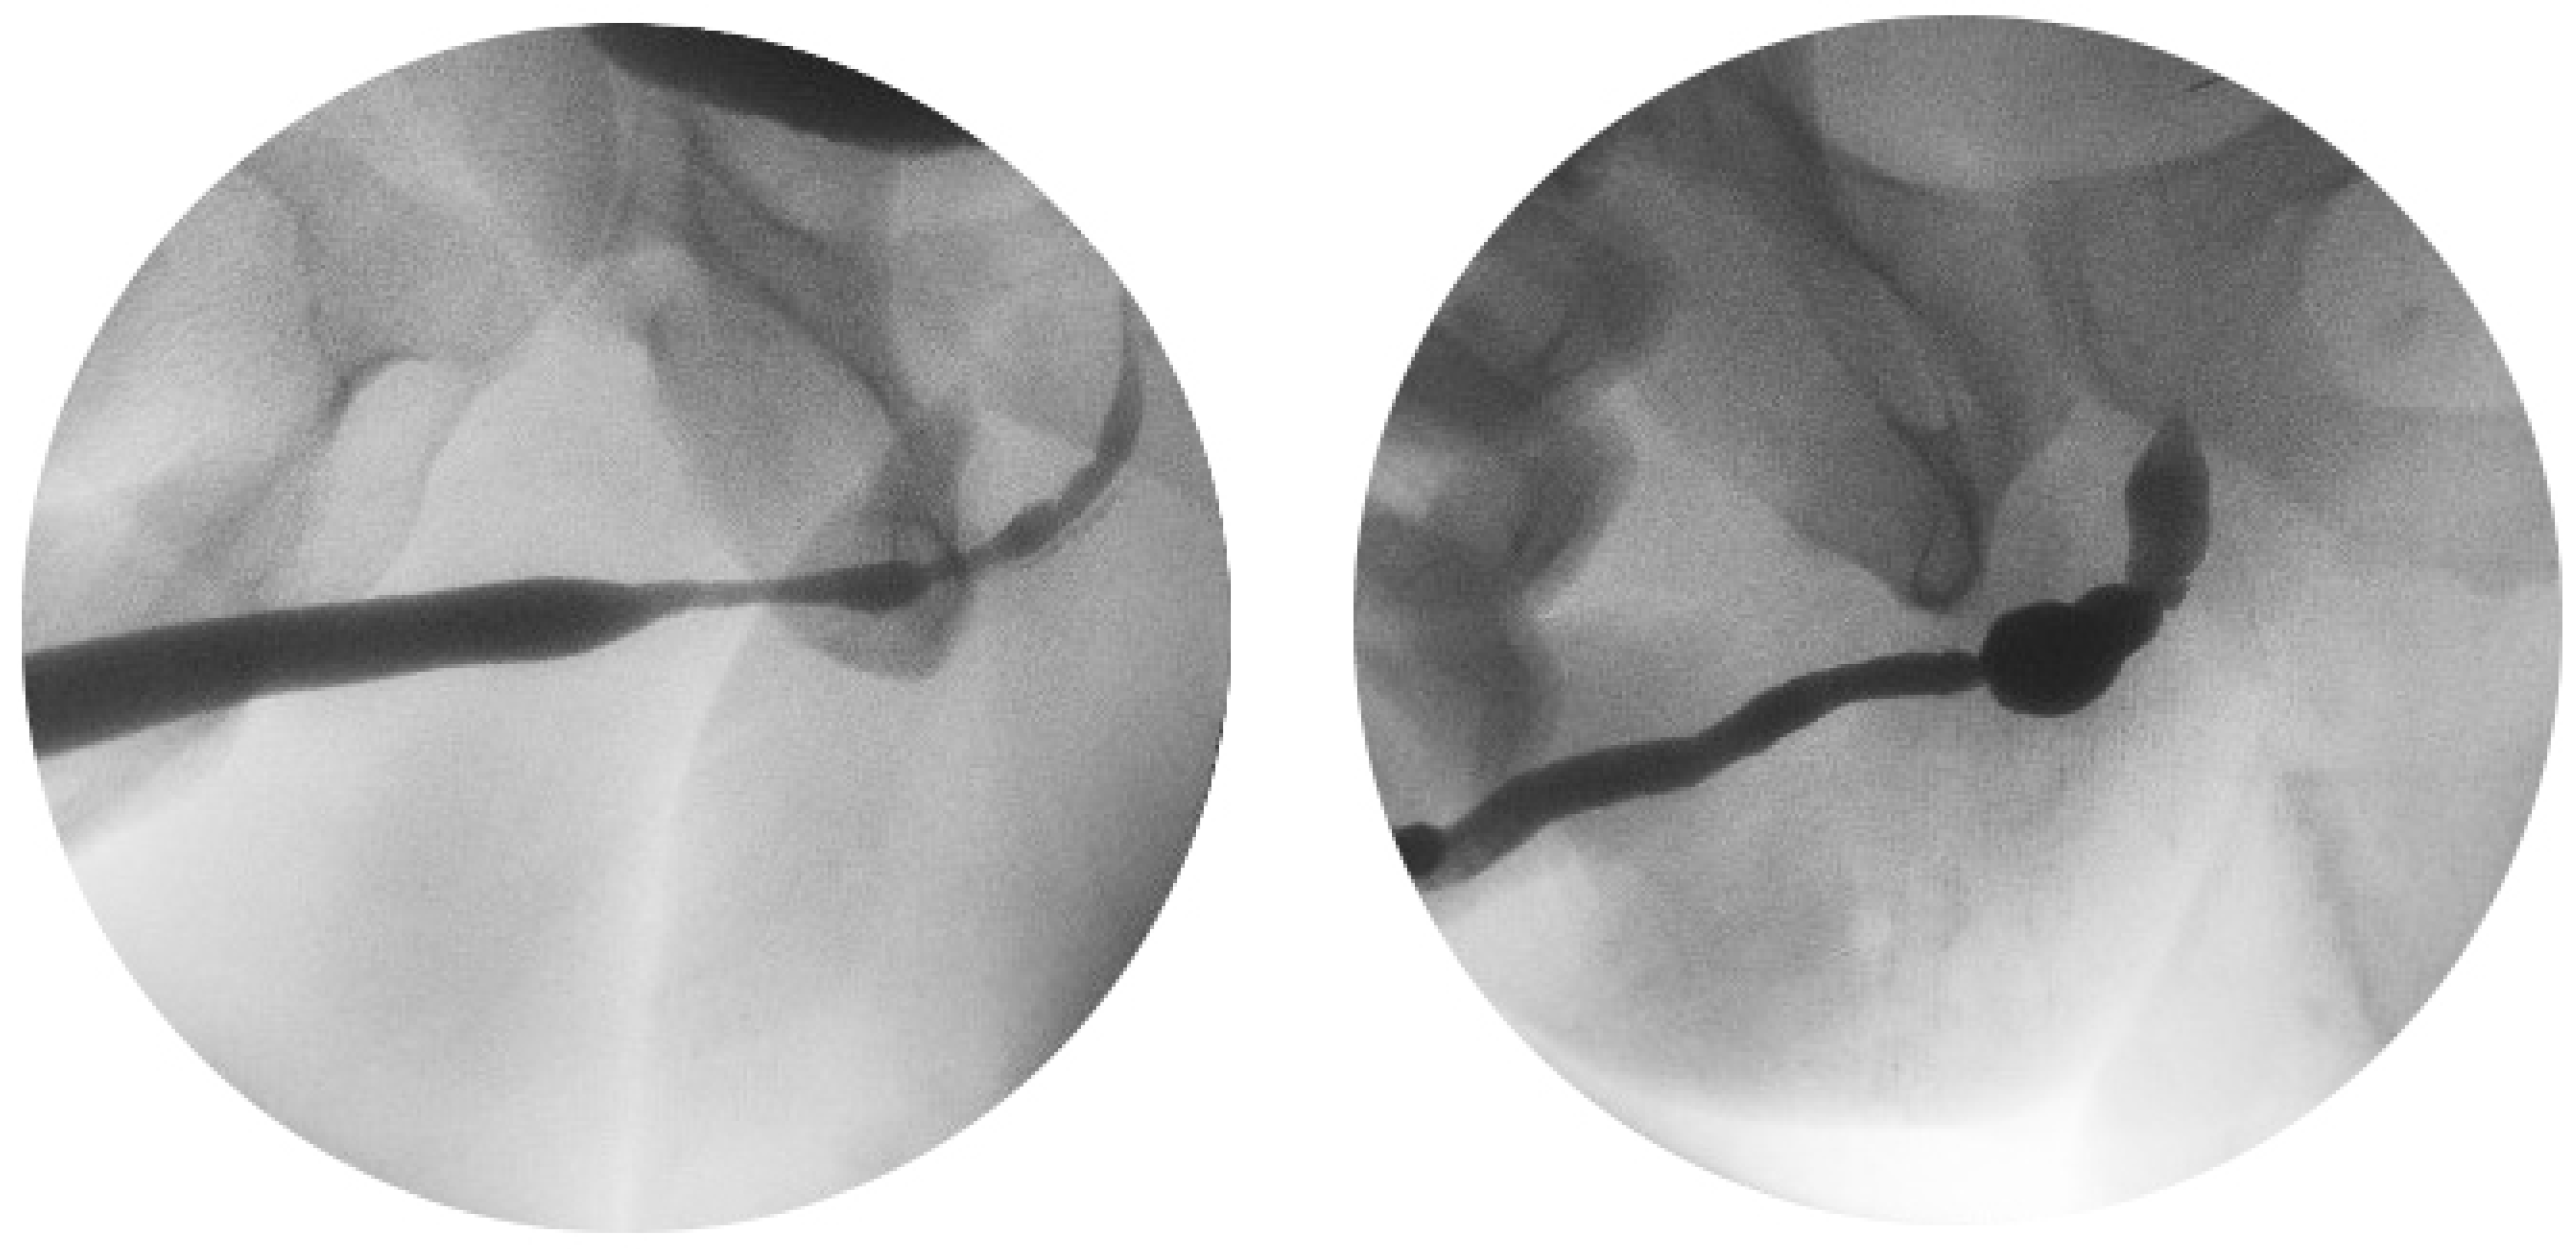

Figure 2.

Examples of retrograde urethrograms where length and characteristics of the strictures cannot be assessed without endoscopic inspection.